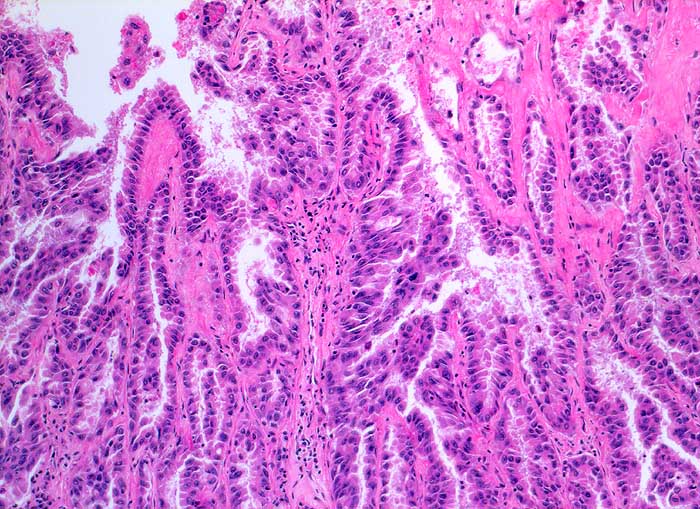

Unten gezeigt werden zwei verschiedene Fälle.